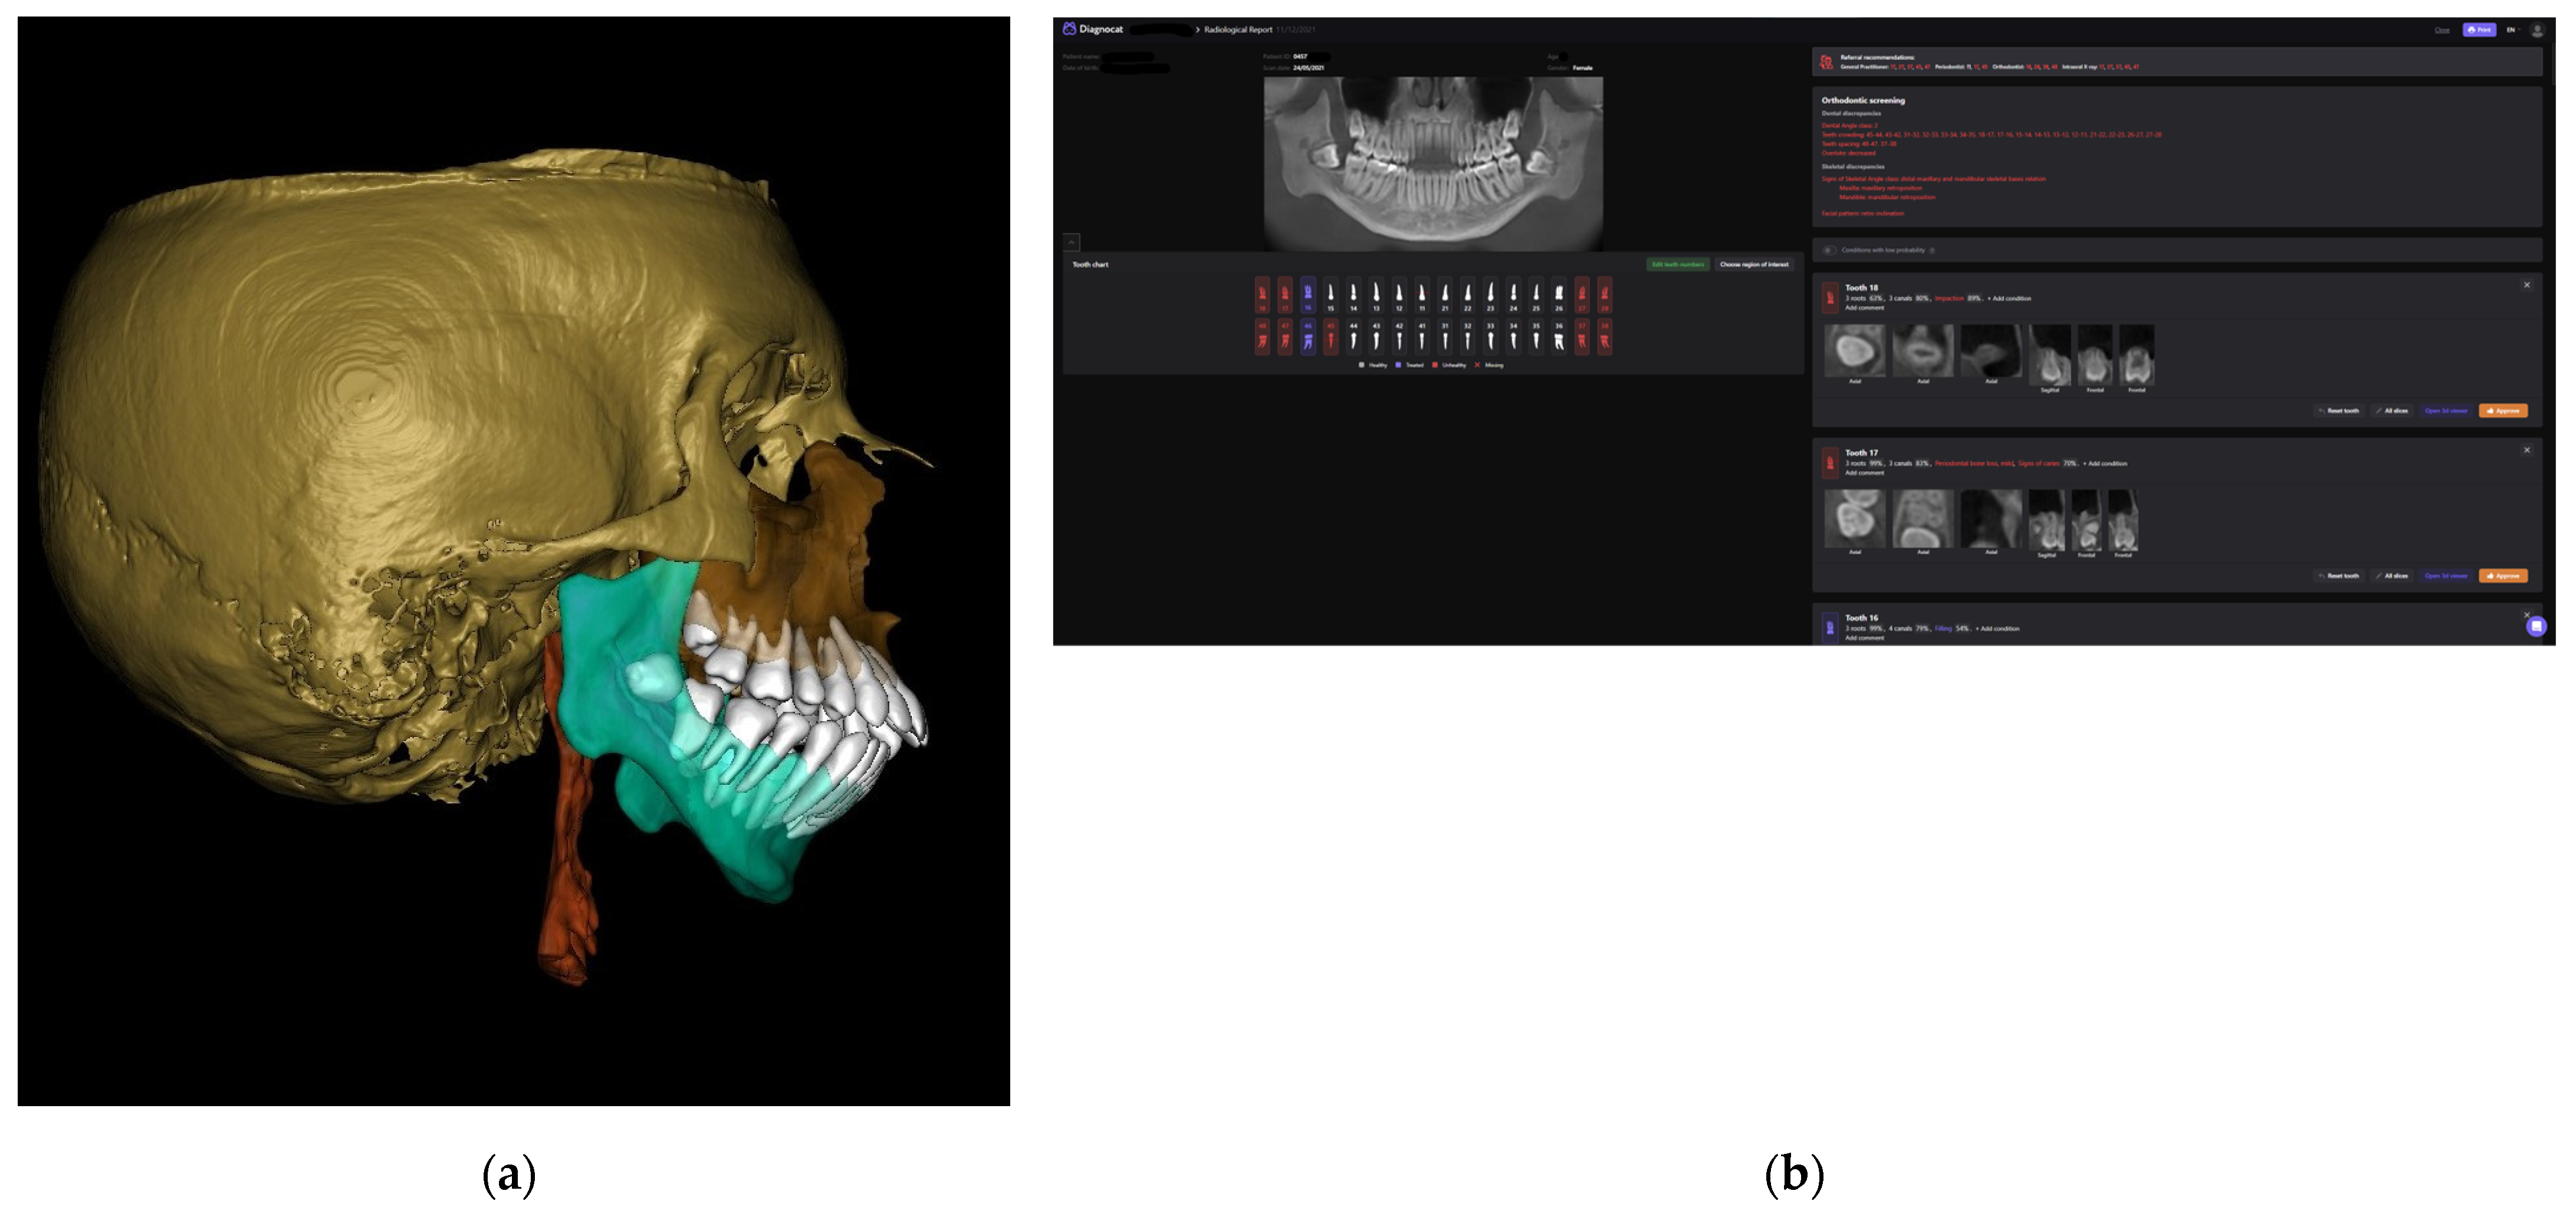

- Diagnocat (USA—Diagnocat LTD, Miami, FL, USA) for AI segmentation;

- Invivo 7.0 (Anatomage, Santa Clara, CA, USA) for segmented model analysis;

2.3. Processing CBCT